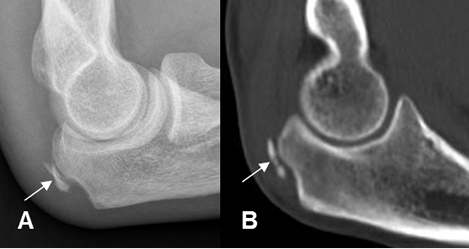

Fig 37 D. Avulsión olecranon.

A: Rx lateral y B: TAC reconstrucción lateral. Fragmento óseo suelto, por avulsión del olecranon.